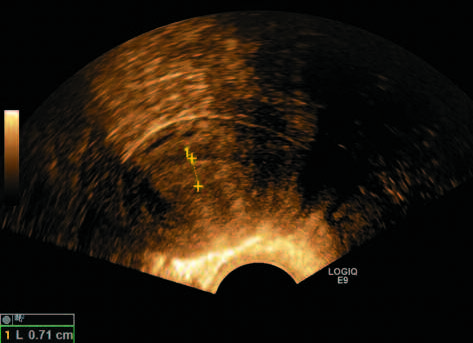

Многие исследования подтверждают данные A. Timmermans и соавт. В частности, исследование A. Wong и соавт. с участием женщин с ПМК показало, что пороговое значение толщины эндометрия 3 мм имеет чувствительность 97% и специфичность 45,3%; значение 4 мм имеет чувствительность 94,1% и специфичность 66,8%, а значение 5 мм имеет чувствительность 93,5% и специфичность 74% для выявления РЭ (рис. 1, 2) [30].

Рис. 1. Пациентка Э., 61 г. ПМК. Толщина эндометрия – 7,1 мм. РЭ (собственные данные).